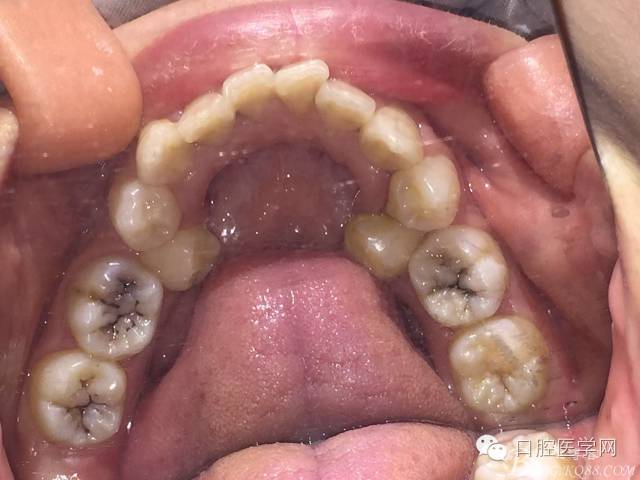

患者 女性 21 主訴:牙齒不齊,面突影響美觀。

重度擁擠減數(shù)雙尖牙時(shí)UL4頰根遠(yuǎn)中彎曲,導(dǎo)致斷根,為防止進(jìn)一步創(chuàng)傷,又怕后期間隙關(guān)閉不順,應(yīng)用擴(kuò)大針將殘根牽引出